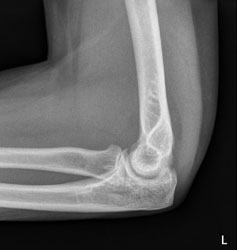

Eine 37 Jahre alte Frau stürzt auf dem Eis zu Boden und stützt sich mit dem linken Arm noch ab. Wegen Schmerzen im linken Ellbogen geht sie zum Arzt, welcher das folgende Röntgenbild macht.

Der erstbehandelnde Arzt sieht auf dem Röntgenbild keine Fraktur und verordnet der Patientin Schmerzmittel. Weil die Schmerzen aber nicht bessern, meldet sich die Patientin wieder und das Röntgenbild wird noch einmal beurteilt: